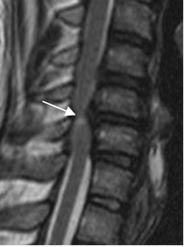

La RM es el estudio de elección para la valoración de la compresión del canal y el estudio de la mielopatía intrínseca por espondilosis o hernia de disco. Tiene la desventaja que no detecta calcificaciones, ni pequeños osteofitos. (13). (Fig 70).

Fig 70. Mielopatía.

RM sagital en T2. Canal estrecho central cervical, que comprime la medula. Hay zona hiperintensa, por mielopatía.